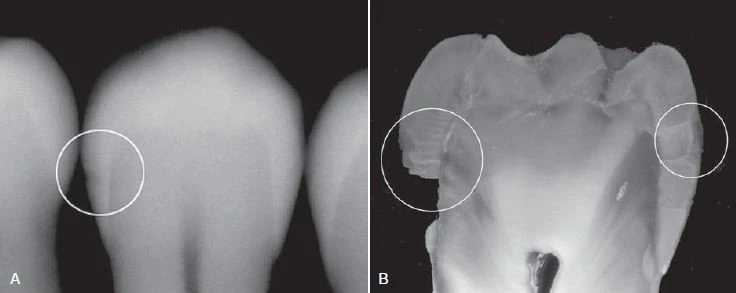

Hình 5. Hình ảnh phóng đại phát hiện sâu men vùng răng cối nhỏ.

Hình 11. A. Hình ảnh X quang của một răng đã được nhổ với tổn thương nằm ở ngà răng phía bên trái (vòng tròn). B. Răng được cắt và soi dưới kính hiển vi cho thấy tổn thương nằm ở cả hai bên, tổn thương bên phải chỉ nằm ở men răng (phần men răng phía bên trái răng bị vỡ trong quá trình cắt)